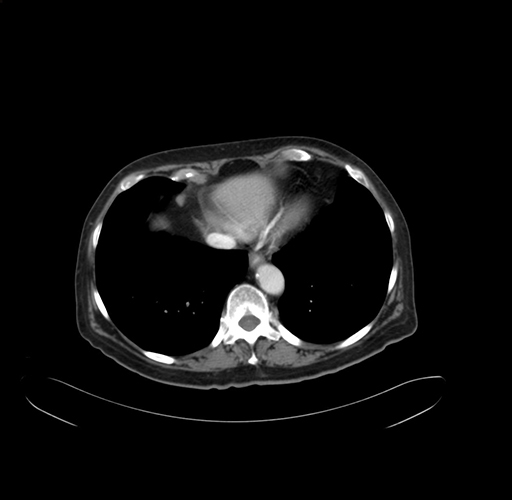

Pre-Chemo: Axial Venous